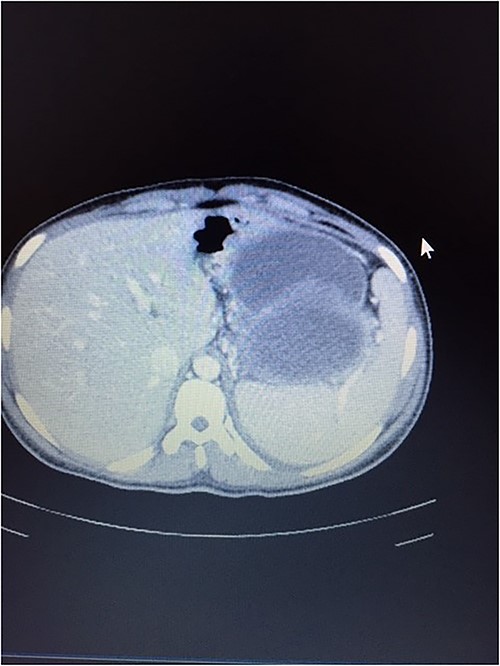

A 21-year-old female collapsed in a market and was taken to a local hospital where she was told that she had a ruptured spleen. She was transfused with two units of whole blood and discharged without surgery. Four weeks later, she noted persistent fullness in her left upper quadrant and presented to our hospital for further evaluation. A contrast CT scan revealed two well-encapsulated, cystic masses in the left upper quadrant, the largest one with small solid components abutting the tail of the pancreas and the smaller one adjacent to the posterior wall of the stomach. She had splenic vein thrombosis, but her portal vein was patent. Numerous portosystemic venous pathways were present, mostly in the gastrosplenic area. The spleen was homogeneous but enlarged with a smooth capsule and normal contour. The liver was normal (Figs. 3 and 4). Her preoperative laboratory studies, including complete blood count, liver function tests, and coagulation studies were normal. A fine-needle aspiration of the anterior mass revealed fresh blood. She was given vaccines against pneumococcus, meningococcus, and haemophilus, anticipating splenectomy would be necessary to resect this mass. At surgery, the splenic artery was ligated at its origin from the celiac axis, which led to an immediate decompression of the peri-splenic and gastric venous collaterals before attempting resection of the mass. The anterior/superior mass was a large, partially organized hematoma, but the inferior mass arose from the tail of the pancreas. A distal pancreatectomy and splenectomy were done en-bloc. The final histopathology revealed a solid pseudopapillary epithelial tumor of the pancreas with negative margins of resection. The patient had an uncomplicated postoperative course and remains asymptomatic.

CT scan showing normal liver and enlarged spleen in close proximity with the mass.